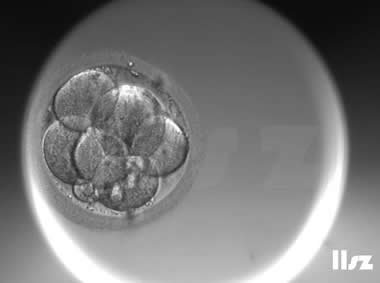

下面视频是胚胎在时差培养箱中培养至D3的整个过程,图片是D3(第68小时)的卵裂期胚胎图,本文D3胚胎评价是以D3时间点图片的形态学为依据,胚胎评级如下:

| Ⅱa级:该枚D3胚胎为8细胞,碎片在10%左右,因此评级为I级或Ⅱa级均可。 | |